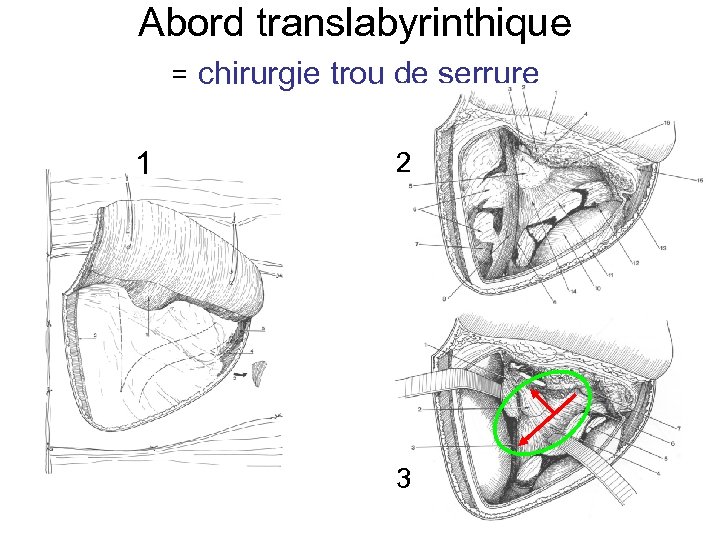

Abord translabyrinthique = chirurgie trou de serrure 1 2 3

Abord translabyrinthique = chirurgie trou de serrure 1 2 3